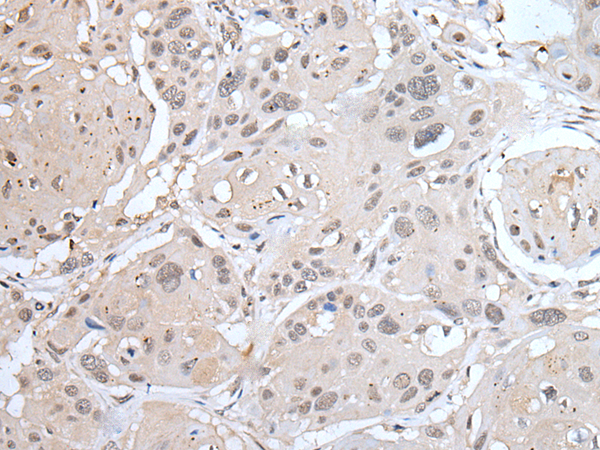

分类: 科研抗体货号: P12757别名: CD129; IL-9R应用: WB,IHC反应种属: Human, Mouse